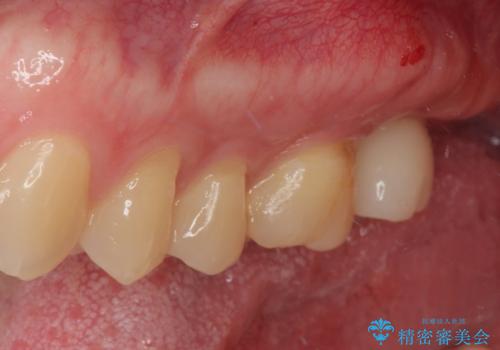

根尖病巣も大きかったため先に抜歯を行い、1ヶ月後にインプラントを埋入しました。

インプラントの埋入から被せものの装着まで2ヶ月で終えることができました。治療期間も短く、しっかり咬めるため大変喜んでいただきました。